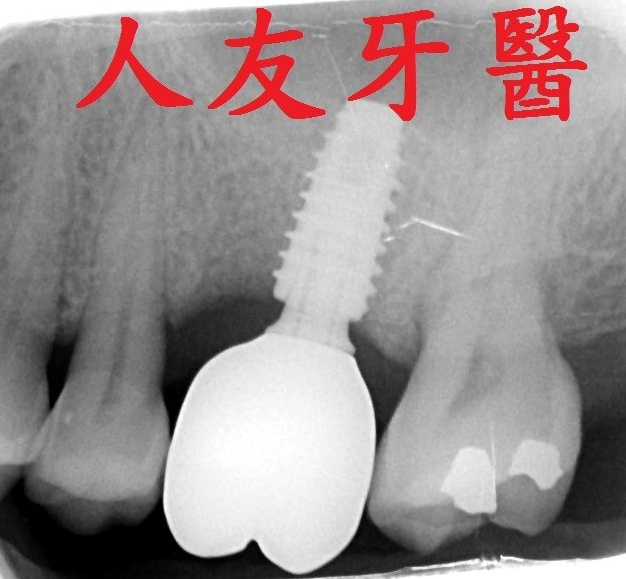

植體周圍炎牙齒從外表看不出來,需從x光片才能看出來,為避免造成植體周圍組織發炎,甚至破壞到周遭骨頭,平時應注重牙齒清潔保養,選擇刷毛軟的牙刷清潔 , 搭配牙間刷去清潔牙縫 , 並定期回診檢查,確保牙齒健康。